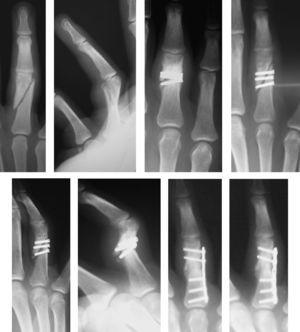

Para llevar a cabo esta técnica se realizó una selección según las características de los pacientes y el tipo de fractura. Es imprescindible que sean pacientes colaboradores y las fracturas subsidiarias de este tipo de tratamiento fueron fracturas inestables que permitían conseguir una buena estabilidad mediante la osteosíntesis con tornillos, como fracturas condíleas de las falanges, fracturas diafisarias espiroideas u oblicuas largas de la falange, fracturas de la base de la falange, fracturas intraarticulares y algunas fracturas de la base del primer metacarpiano (figura 1,figura 2,figura 3,figura 4).

Figura 1. Fractura oblicua larga extraarticular de la falange media del dedo medio.

Figura 2. Fractura de la base de la falange media del dedo anular.

Figura 3. Fractura de cóndilo de la falange proximal del dedo índice.

Figura 4. Fractura de la base del primer metacarpiano.